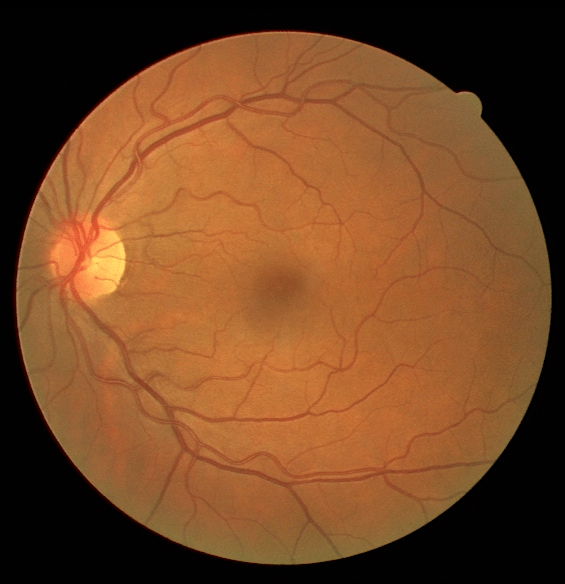

III The RAVIR Dataset

Recently there has been a substantial increase in the utilization of single wavelength confocal imaging that only captures reflected light passing through a pinhole, which will allow capturing high quality, high contrast fundus images. The images in our RAVIR dataset were captured using infrared (815nm) Scanning Laser Ophthalmoscopy (SLO), which in addition to having higher quality and contrast, is more convenient for the patient and is less affected by opacities in optical media and pupil size. This imaging modality is also commonly used in ophthalmology clinics. The RAVIR dataset consists of 46 IR retinal images from the UCLA Stein Eye Institute imaging database, divided into train and test sets of 26 and 20 images, respectively. We used 4 images from the 26 test images as our validation set. The images were captured using a Heidelberg Spectralis camera with a FOV. They are sized at pixels and compressed in the Portable Network Graphics (PNG) format. Each pixel in the images has a reference length of 12.5 microns. Table I compares our RAVIR dataset against other retinal vessel segmentation datasets.

VI-A Retinal Artery and Vein Segmentation

As reported in Table IV, we compared the SegRAVIR model against competing deep learning-based segmentation approaches on the RAVIR dataset. Evidently, SegRAVIR outperforms these methods as judged by all metrics for artery and vein classes with a healthy margin. In terms of Dice score, SegRAVIR outperforms CE-NET, IterNet and AG-Net by , and for artery segmentation and by , and for vein segmentation, respectively. Fig. 4 presents a qualitative comparison of the semantic segmentation outputs of SegRAVIR, CE-Net, and U-Net. Specifically, SegRAVIR yields more accurate vessel topology (i.e., thickness and orientation) segmentation with higher pixel-wise classification accuracy.